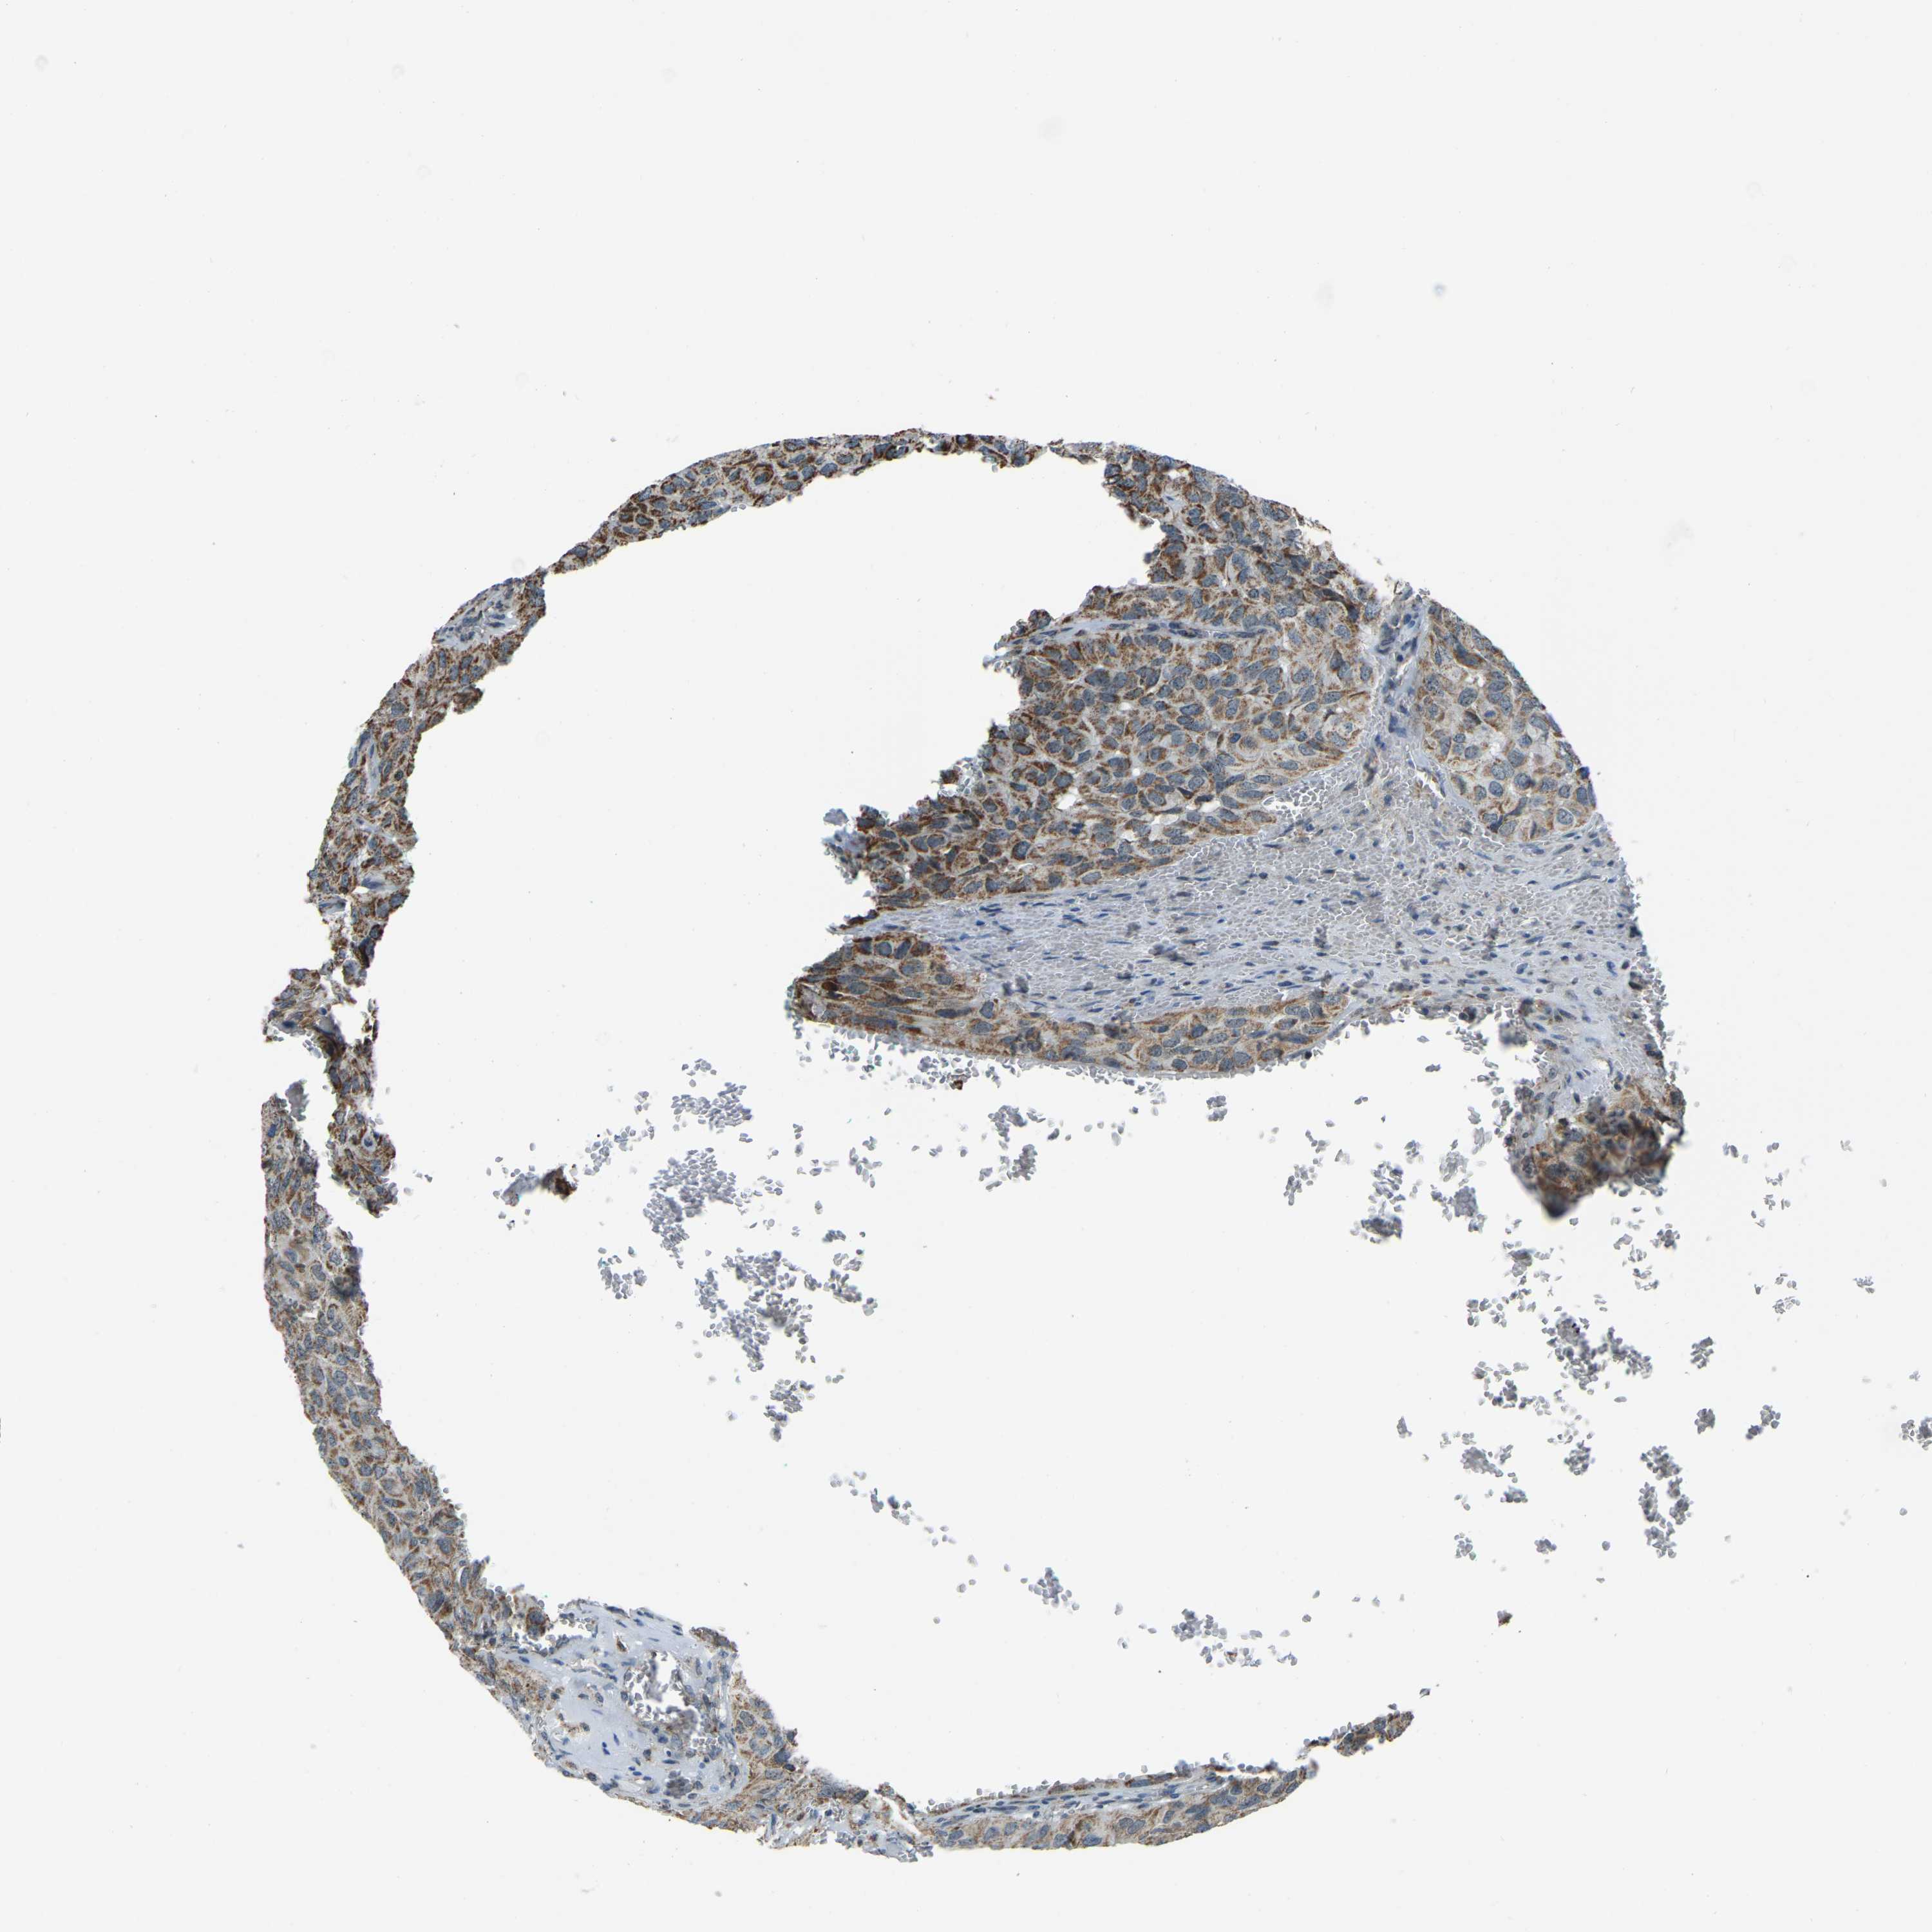

HEAD AND NECK CANCER - Protein expressioni

A mouse-over function shows sample information and annotation data. Click on an image to view it in a full screen mode. Samples can be filtered based on level of antibody staining by selecting one or several of the following categories: high, medium, low and not detected. The assay and annotation is described here.

Antibody stainingi

Antibody staining in the annotated cell types in the current human tissue is reported as not detected, low, medium, or high, based on conventional immunohistochemistry profiling in selected tissues. This score is based on the combination of the staining intensity and fraction of stained cells.

Each image is clickable and will lead to virtual microscopy that enables deeper exploration of all samples and also displays staining intensity scores, fraction scores and subcellular localization as well as patient and tissue information for each sample.

Antibody HPA019232

Antibody HPA021497

Antibody HPA021768

Staining

High

Medium

Low

Not detected

Intensity

Strong

Moderate

Weak

Negative

Quantity

>75%

75%-25%

<25%

None

Location

Nuclear

Cytoplasmic/membranous

Cytoplasmic/membranous,nuclear

Squamous cell carcinoma, NOS

Squamous cell carcinoma, metastatic, NOS

Adenocarcinoma, NOS